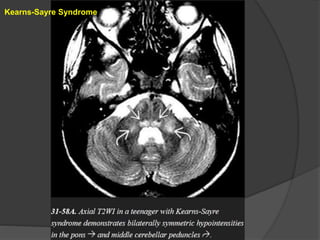

Kearns-Sayre Syndrome KSS typicallypresents in older children or young adults and is characterized by short stature, progressive external ophthalmoplegia, retinitis pigmentosa, sensorineural hearing loss, and ataxia. Imaging CT scans show variable symmetric basal ganglia calcifications. Mild cortical and cerebellar volume loss is common. MR shows increased signal intensity in the basal ganglia, WM, and cerebellum on T2/FLAIR. The subcortical arcuate fibers, corticospinal tracts, cerebellum, and posterior brainstem are involved early in the disease course while the periventricular WM remains relatively spared. DWI shows reduced diffusivity in the brainstem and subcortical WM. MRS demonstrates elevated lactate.